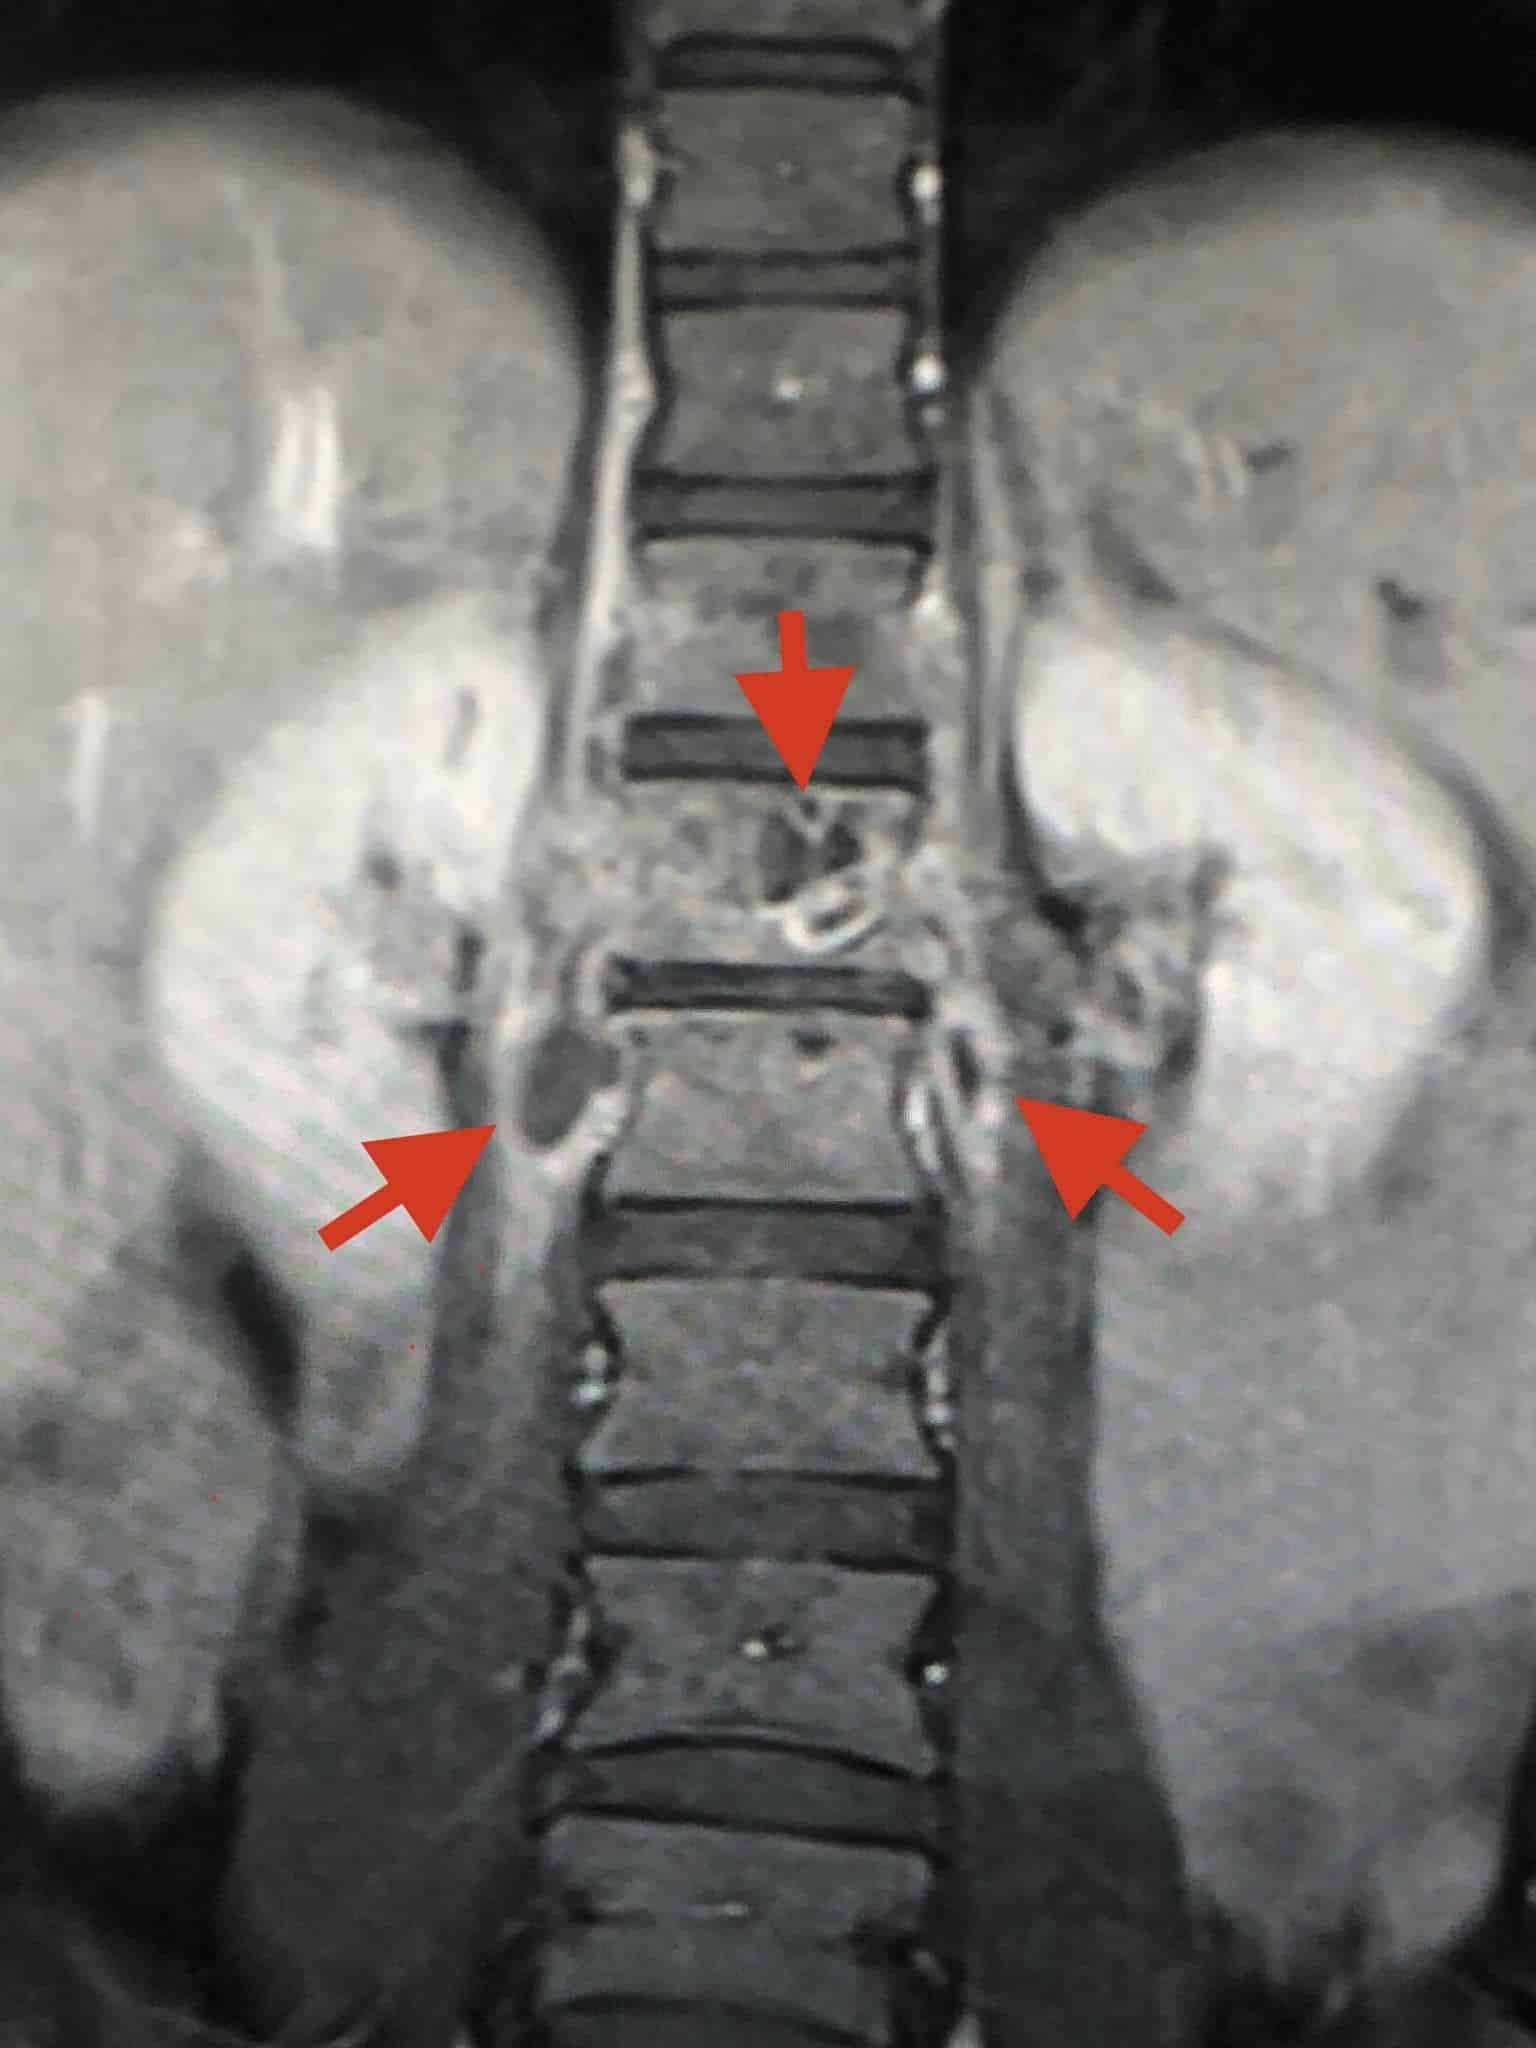

ตรวจร่างกายปกติ เจาะเลือดทุกอย่างปกติ เอกซเรย์ปอดและกระดูกสันหลังส่วนเอวปกติ ทำคลื่นแม่เหล็กไฟฟ้ากระดูกสันหลังส่วนเอว (MRI lumbar spine) ผิดปกติ สงสัยเป็นวัณโรคของกระดูกสันหลังส่วนเอว (lumbar spine) ชิ้นที่หนึ่ง และสงสัยมีการอักเสบรอบ ๆ เนื้อเยื่อกระดูกสันหลังส่วนเอวชิ้นที่ 1 และ 2 ร่วมด้วย (ดูรูป)